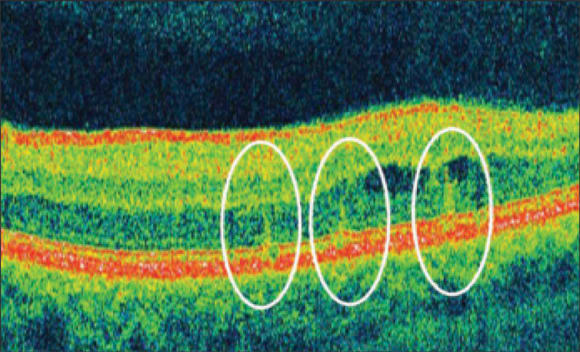

Figure 2. Imaging with the 3D OCT 1000 (Topcon), obtained 1 hour post PASCAL treatment, shows that the laser coagulative effects are limited to the outer retina. Burns have been circled for easier identification.

With PASCAL, we attempt to make very light burns. We have observed, for example, in a patient with thickening of the macula temporal to the fovea, that not all of the burns in a pattern were visible. Red-free photography more clearly showed them. Using autofluorescence an hour later, all of the burns were visible, including those used to titrate the treatment intensity. The burns looked hypo-autofluorescent; they lacked an autofluorescence signal. In the same patient, Fourier domain optical coherence tomography (OCT) indicated that the burns were confined to the outer retina. This correlates well with the histopathology work of Mark Blumenkranz, MD, and his colleagues, who similarly found the PASCAL treatment effect in such cases to be confined to the outer retina.1,2

Our interpretation of the autofluorescence images was that the hyper-autofluorescence represented the accumulation of lipofuscin that resulted from either targeted photoreceptor or RPE cells. Fourier domain OCT showed that the PASCAL burn was confined to the RPE or the space between the RPE and the junction between the inner and outer layers of the photoreceptors.